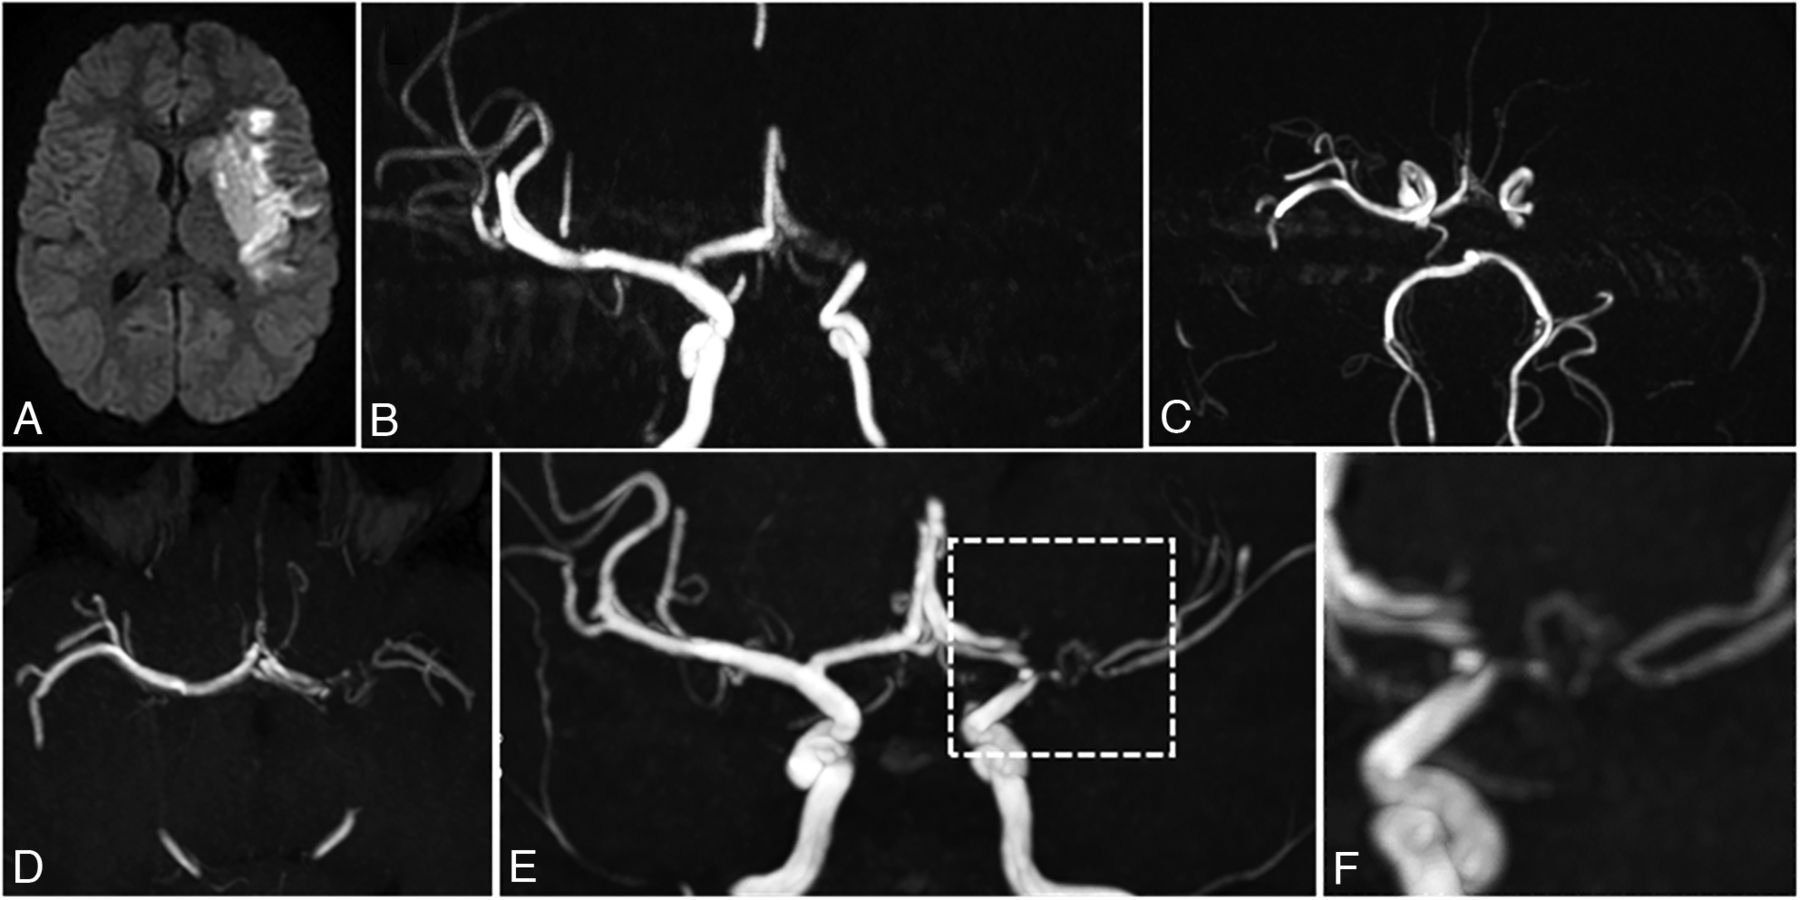

U-PS anastomotic bridge development in a patient with AIS and LVO, and unilateral FCA. Upper panel: acute phase MR imaging, showing recent MCA infarction with DWI hypersignal (A), with proximal left MCA occlusion and left A1 stenosis on the time-of-flight MRA, coronal view MIP 15 mm (B) and axial view MIP 10 mm (C). No collateral is visible at the acute phase. Lower panel: MR imaging 12 months after stroke occurrence. Time-of-flight MRA shows strictly unilateral left anomalies. Axial view (D) shows a reverted to normal left A1 segment and a persisting steno-occlusive M1 lesion, favoring the diagnosis of FCA. E, Coronal view shows a U-PS anastomotic bridge bypassing the M1 occlusion, with distal visible flow. F, Closer view of the U-PS anastomotic bridge illustrates the collaterals direction, parallel to the main MCA trunk, without perforating lenticulostriate collaterals.